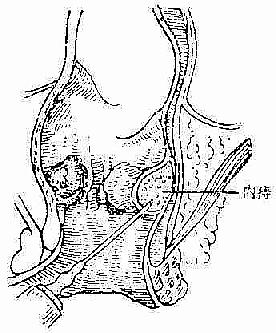

操作方法 病人排空大便,胸膝位肛镜下显露痔块,消毒后在齿线上方针头刺入粘膜下层注药,每个痔块注射1~2ml(图2-109)。

图2-109 内痔注射疗法